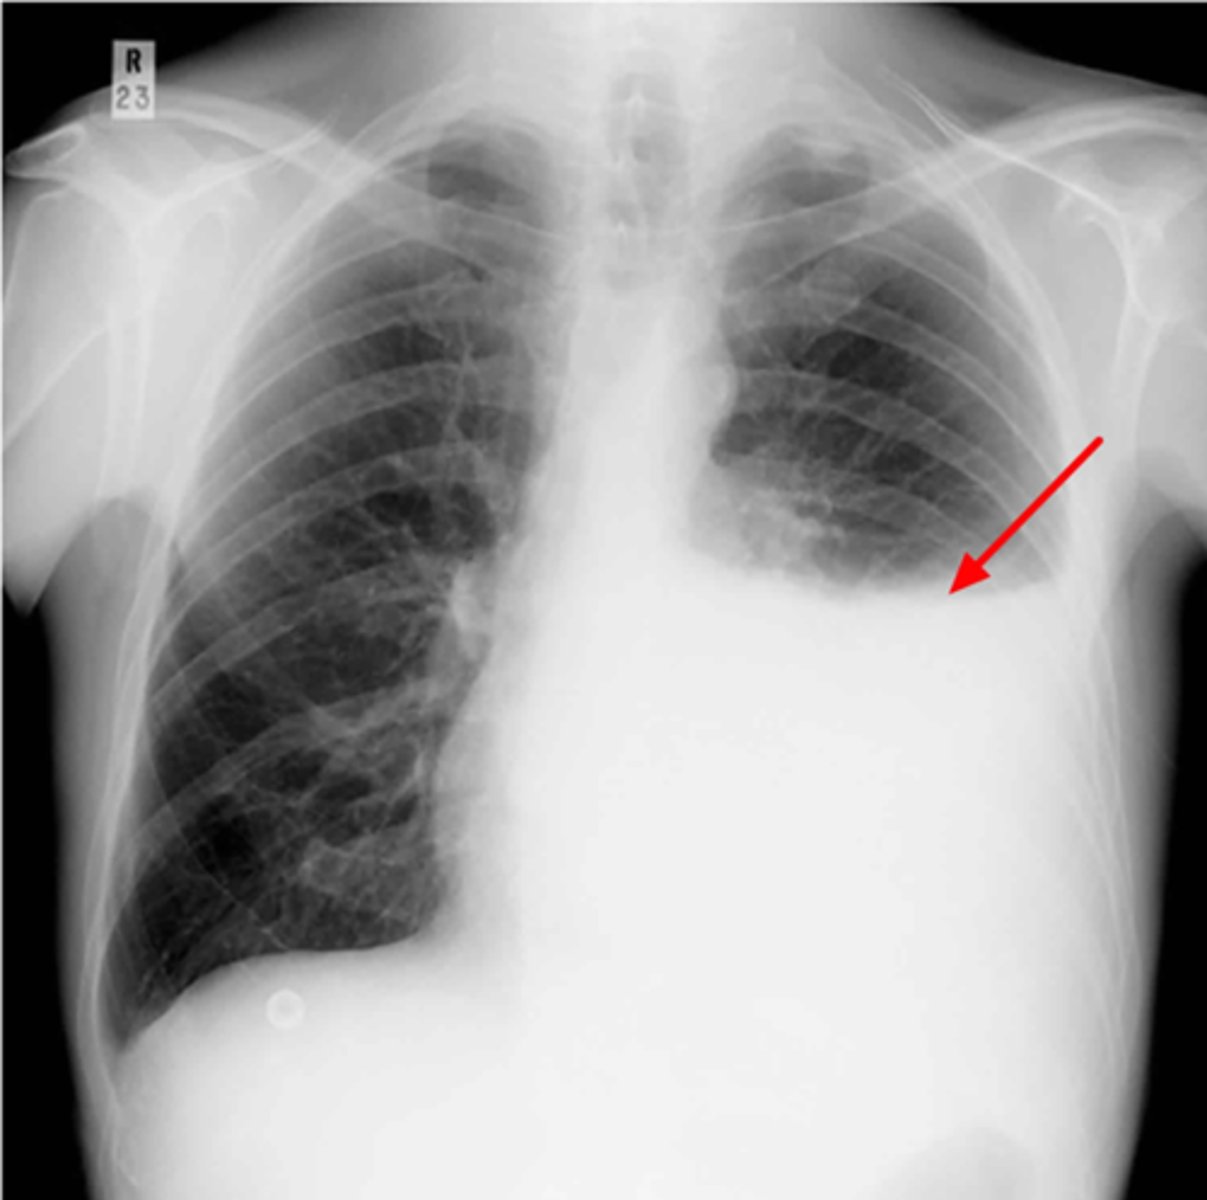

Left lung

Where is the abnormality located in the chest?

Atelectasis

What is the red arrow indicating?

Effusion

What is the likely interpretation?